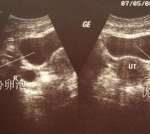

那么你服药多久了?服药后有没有做超声波检查,观察子宫内膜的变化?如果现在是6mm,那就是子宫内膜太薄,种植不成功。一般要接近10mm才能种植成功。所以最好观察五天左右,复查内膜再决定。

宫腔镜只能看到子宫内膜的情况,对子宫内膜没有治疗作用:胚胎移植前需要做宫腔镜,因为不了解子宫内膜的情况下盲目移植会导致流产。如果子宫内膜的环境不理想,后期可以调整移植。